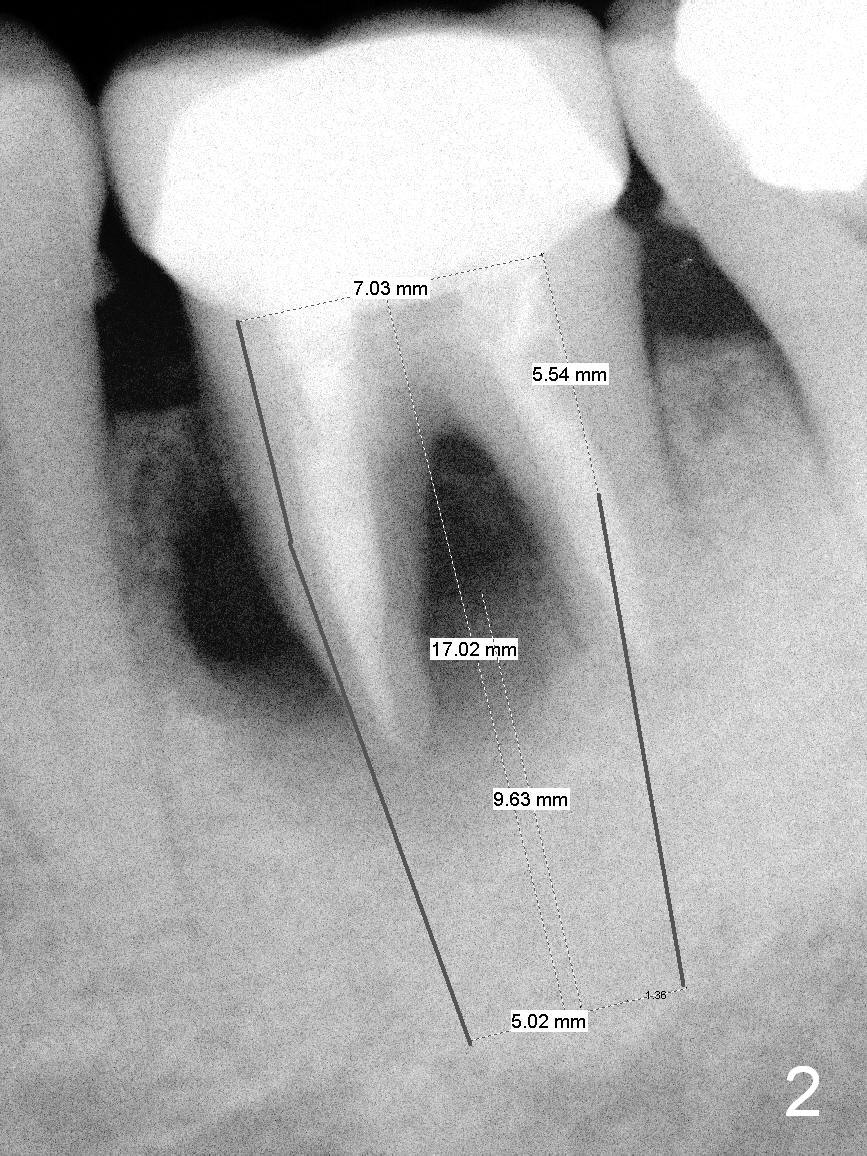

The tooth #19 of a 54-year-old man (FJ) looked normal 2.5 years ago (Fig.1).  The patient returns because of 3 fistulae developing around the mesial root of the tooth.  Recent PA shows a large radiaolucent defect (Fig.2,3).  To place an implant in the middle of the edentulous space, initial osteotomy should be distal because of the large mesial defect.